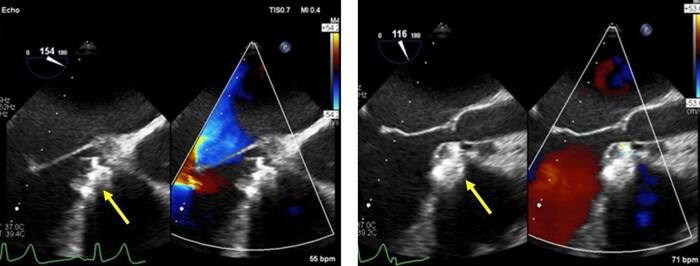

A 34-year-old male with known VSD was referred for transcatheter closure after failed attempts in other hospital. Patient had been diagnosed with VSD at a young age, but he was lost to follow-up. He presented with shortness of breath due to heart failure and pulmonary hypertension. The initial measurement of the defect was 6-7 mm by transthoracic echocardiography (TTE), transoesophageal echocardiography (TEE), and LV angiography. However, re-measurement using TEE and 3D echocardiography revealed that the VSD is oval with diameters of 18 mm × 6 mm. Initially, device No. 12/14 was used, but it was dislodged on two attempts. The operator then decided to upsize the device size to No. 16/18 that was successful. The patient's condition was good, and 6 months follow-up after the procedure showed good outcomes without any residual defect or arrhythmia.

In this study, we would like to highlight the rarity of large oval pmVSD that almost failed to be closed with the conventional measurement with echocardiography and fluoroscopy. Transoesophageal echocardiography especially 3D can be the new modality of choice that might be superior to fluoroscopy to decide the right device size in some cases such as oval-shaped pmVSD.